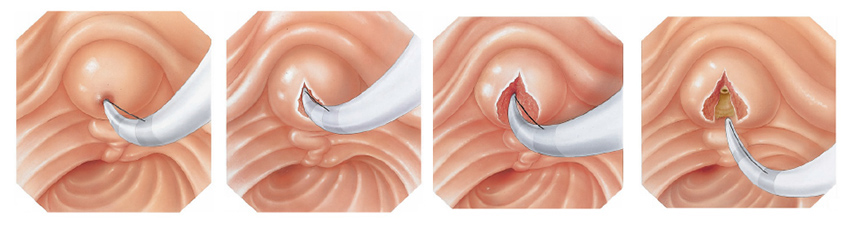

A CPRE pode ser utilizada para o tratamento de pedras ou bloqueios nos canais biliares. Seu médico pode usar alguns acessórios para fazer um pequeno corte na parede do intestino, na abertura do duto biliar comum para alargar a abertura da papila duodenal. Este procedimento chama-se papilotomia endoscópica.

Realizada em quase todos os exames de colangiopancreatogragia retrógrada endoscópica (CPRE), a papilotomia endoscópica é o procedimento de abertura do ducto biliar comum. Tem o objetivo de alargar a abertura da papila duodenal para a drenagem da bile com maior facilidade e para retirada de cálculos que podem estar obstruindo a saída da bile. Também é utilizada em cados de estreitamentos da via biliar, para que se possa utilizar os instrumento de dilatação como as próteses plásticas ou autoexpansíveis.

Apesar da palilotomia por endoscopia ser menos agressiva que a realizada por cirurgia, ela também possui riscos, como sangramento e perfuração do intestino delgado. Estas quando ocorrem, geralmente são tratadas no mesmo momento por endoscopia, mas eventualmente pode haver necessidade de realização de cirurgia para a correção do problema.

Após este diagnóstico realiza-se o procedimento de papilotomia endoscópica, para poder alargar a saída do canal da bile. Com isto pode-se retirar as pedras da via biliar e permitir o retorno normal da drenagem da bile do fígado para o duodeno.

A CPRE pode ser utilizada para o tratamento de pedras ou bloqueios nos canais biliares. Seu médico pode usar alguns acessórios para fazer um pequeno corte na parede do intestino, na abertura do duto biliar comum para alargar a abertura da papila duodenal. Este procedimento chama-se papilotomia endoscópica.